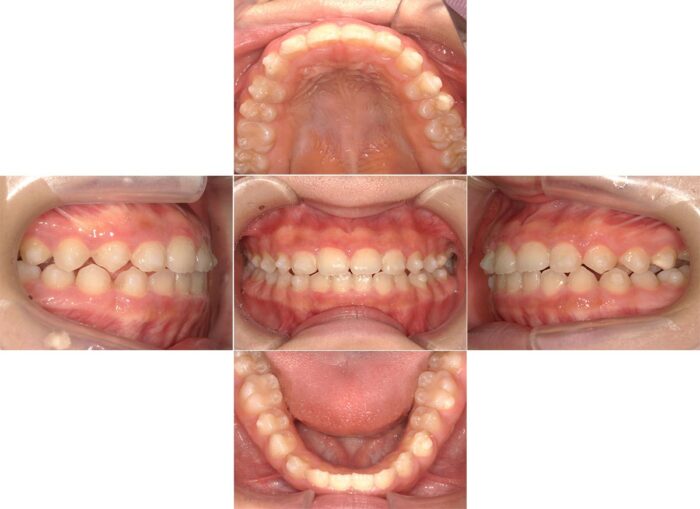

出っ歯とすきっ歯の改善を希望されて相談にいらした患者さまです。口元の突出感が気になるとのことだったので、抜歯矯正をお勧めしましたが、患者さまのご希望で歯を抜かずに治療を開始しました。

治療を始めてから半年が経過したころ、患者さまからご相談があり治療方法を変更することになりました。

やっぱり口元が気になるので歯を抜きたいです

先ほどご紹介したように、ガタガタのない歯列の歯を抜く場合、隙間を閉じるための歯の移動距離が長く、マウスピース単独だと治療に時間がかかる症例です。

隙間が閉じるまでワイヤー矯正で進め、隙間が閉じたらマウスピースに戻ってかみ合わせを調整する方針で治療を再スタートしました。

矯正治療で歯を抜くか抜かないか迷っている方へ、歯を抜く決心がついた時は早めに教えてくださいね!

歯を抜いたことで横顔の変化が大きく、気にされていた口元の突出が解消されました。

食事(特に給食)のたびにマウスピースを外すことが負担だったそうで、結局マウスピースに変更せず、最後までワイヤーで治療を行いました。

【マウスピースから全体ワイヤー矯正に変更した症例詳細】

- 主訴:口元の突出

- 診断名:上下顎前突

- 初診時年齢:12歳・女性

- 使用装置:マウスピース矯正装置(インビザライン)、表側ワイヤー矯正

- 抜歯部位:上下左右第一小臼歯

- 治療期間:2年10ヶ月

- 費用:865,000円(税込951,500円)

- リスクと副作用:痛み、歯根吸収、歯肉退縮、むし歯、後戻り